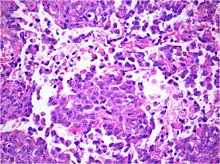

AT/RT and rhabdoid tumor share the term "rhabdoid" because under a microscope, both tumors resemble rhabdomyosarcoma.

The tumor histopathology is jumbled small and large cells. The tissue of this tumor contains many different types of cells including the rhabdoid cells, large spindled cells, epithelial and mesenchymal cells, and areas resembling primitive neuroectodermal tumor (PNET). As much as 70% of the tumor may be made up of PNET-like cells. Ultrastructure characteristic whorls of intermediate filaments are seen in the rhabdoid tumors (as with rhabdoid tumors in any area of the body). Ho and associates found sickle-shaped embracing cells, previously unreported, in all of 11 cases of AT/RT.[16]